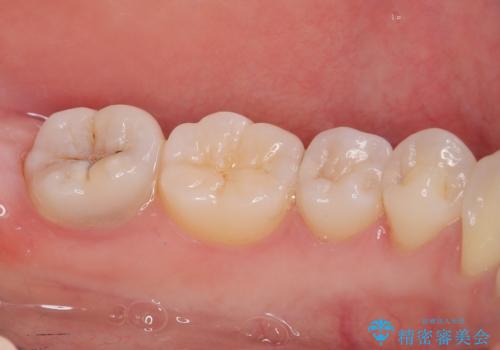

見た目、機能面共に大変喜んでいただきました。

歯と歯の間の虫歯をコンポジットレジンや保険のメタルインレーで治すと段差ができたりして清掃性が悪くなるので、セラミックインレー修復やゴールドインレー修復などの適合の良い詰め物で治療することをオススメします。